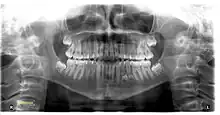

Tooth regeneration is a stem cell based regenerative medicine procedure in the field of tissue engineering and stem cell biology to replace damaged or lost teeth by regrowing them from autologous stem cells.[1]